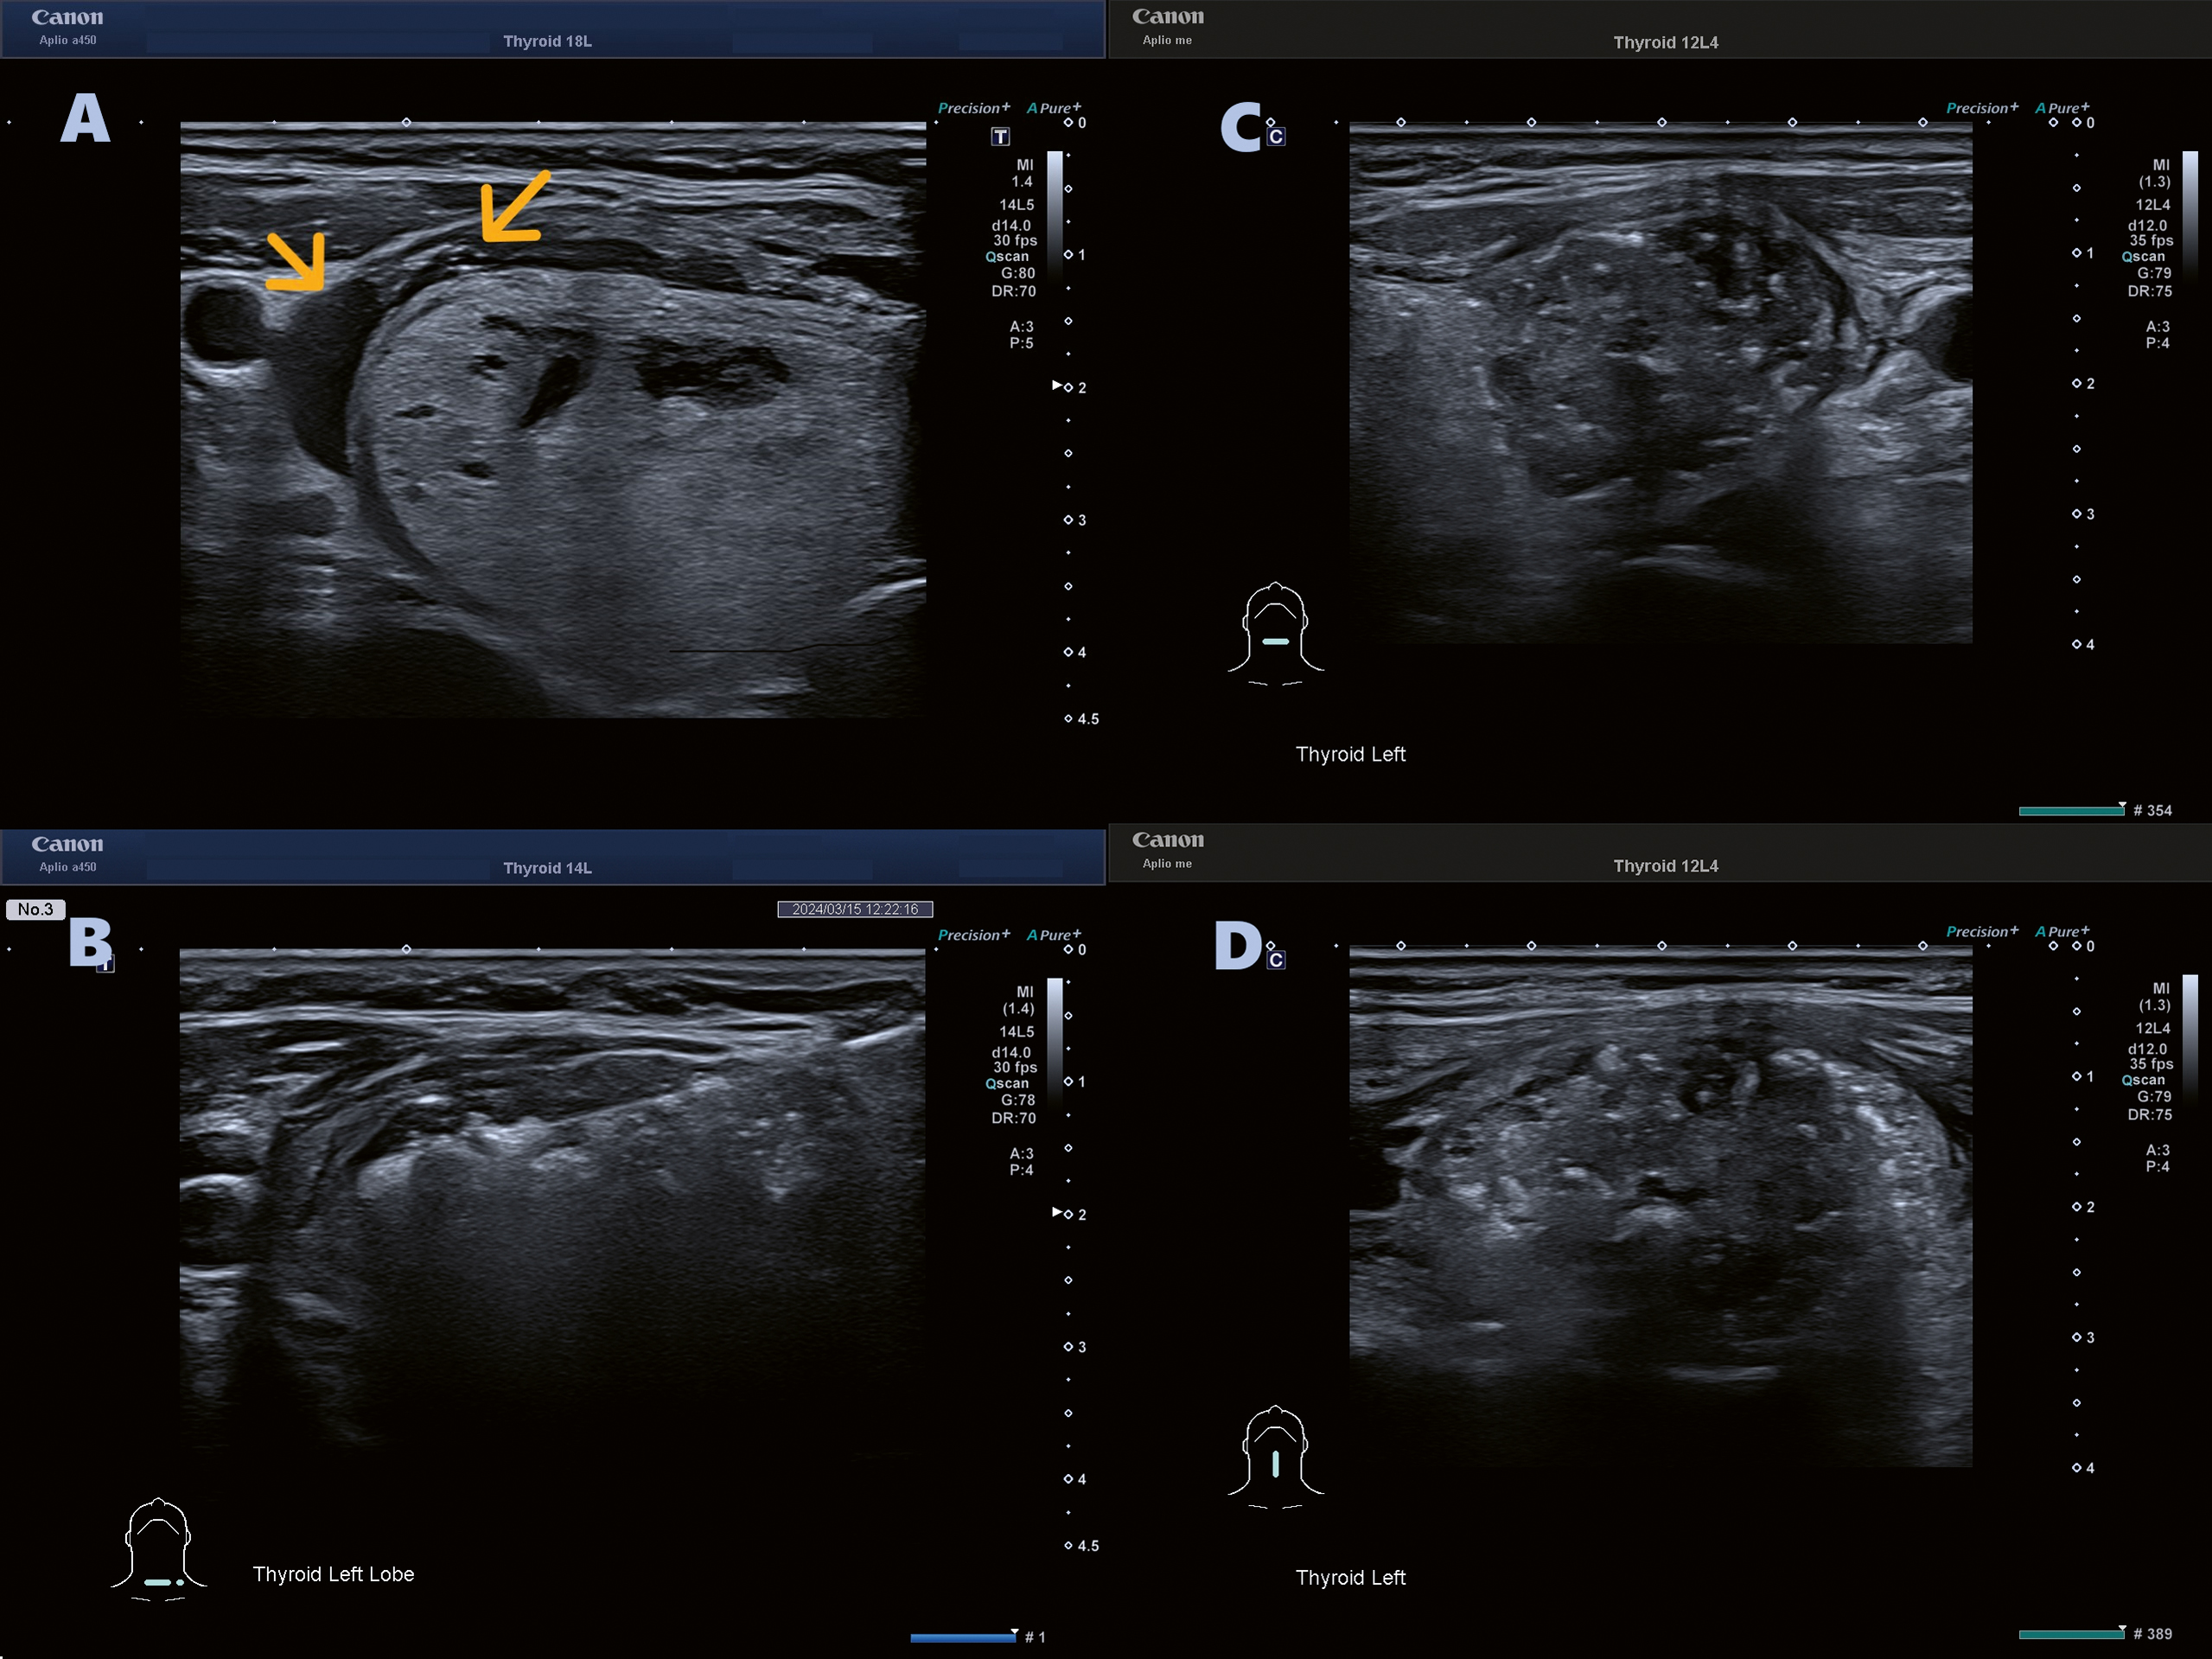

Ablationen genomfördes i lokalbedövning. För att skydda närliggande strukturer, såsom arteria carotis och nervus vagus, injicerades 5 procent glukoslösning för hydrodissektion hos de flesta patienterna (n = 12)  (Figur 1A).

Figur 1. A. För att skydda närliggande strukturer, såsom arteria carotis och nervus vagus, injicerades 5 procent glukoslösning för hydrodissektion (gula pilar). B. RFA-­behandling med »moving shot«-teknik, där elektroden successivt förflyttades genom nodulen. C och D. Hyperekoiska förändringar efter RFA (bild tagen strax efter behandlingen).

RFA utfördes utfördes med realtidsultraljud (Figur 2); elektroden fördes genom istmus och nodulen abladerades med »moving shot«-tekniken [10] (Figur 1B).

Röstfunktion och smärtsensation övervakades kontinuerligt under proceduren för att minimera risken för termisk skada. Vid otillräcklig smärttolerans reducerades effekten eller avbröts temporärt i några se­kunder. Ablationen avslutades när hela nodulen uppvisade övergående hyperekoiska förändringar (Figur 1C och D.)